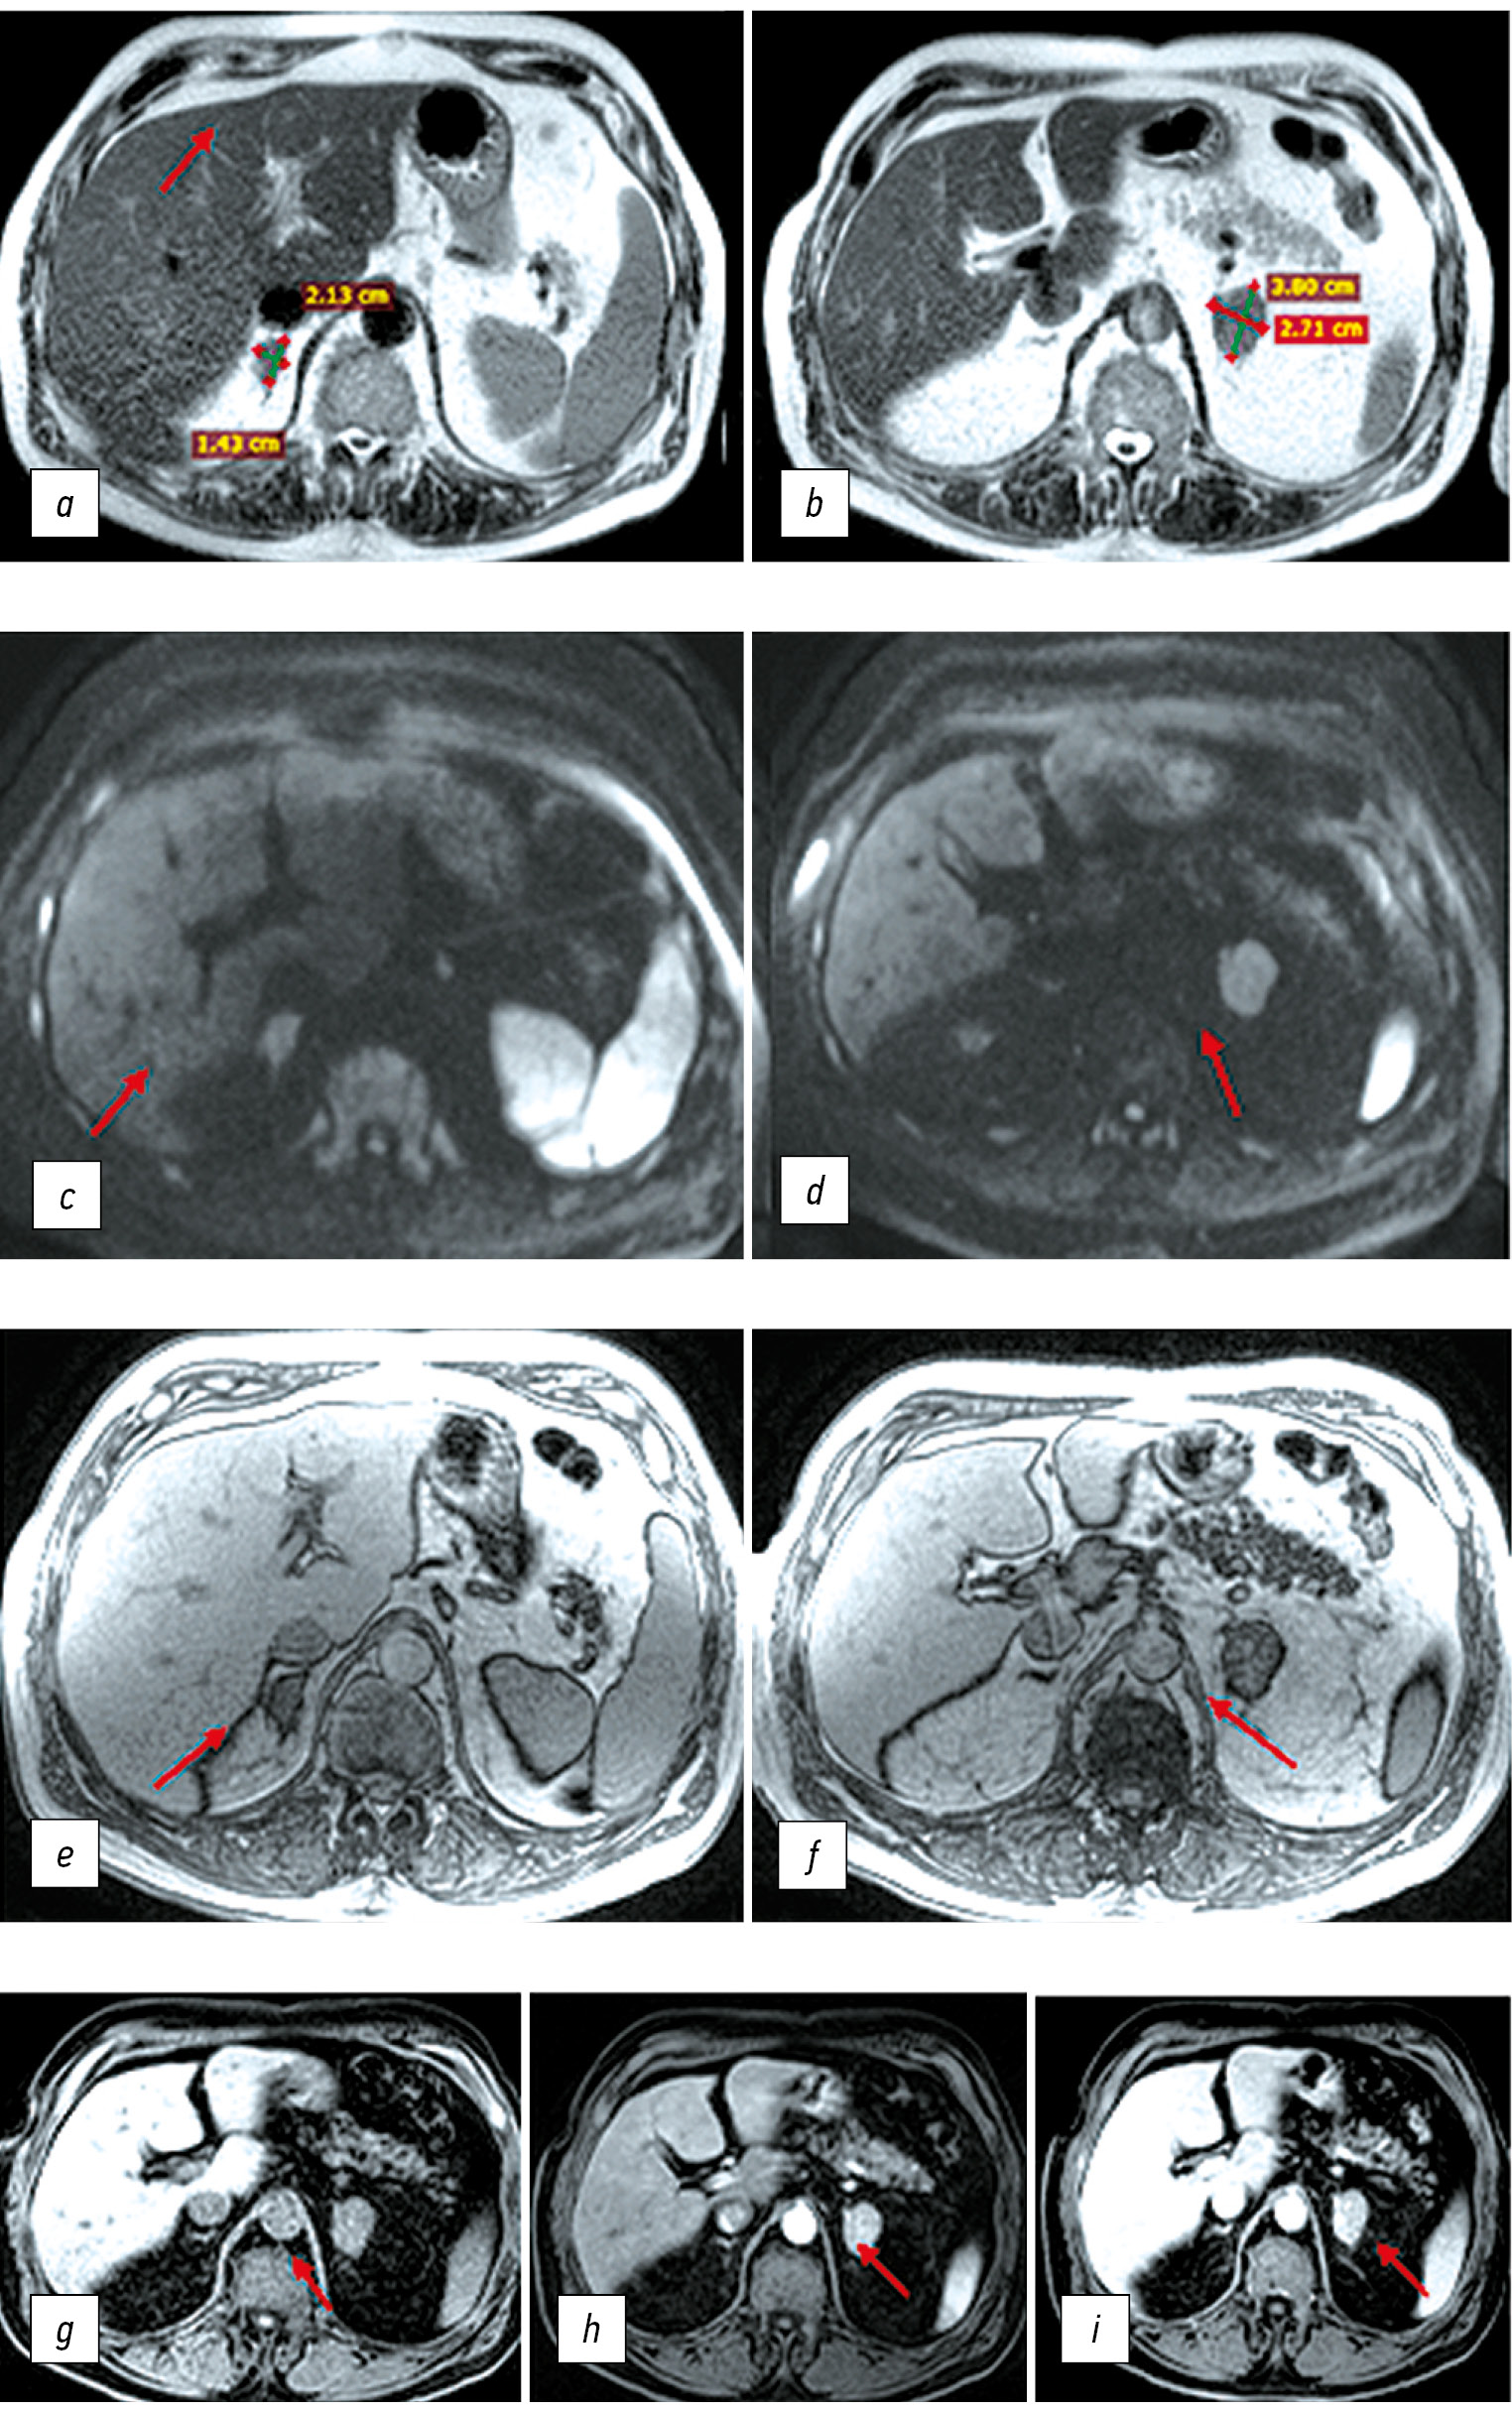

При пересмотре диска магнитно-резонансной томографии (рис. 2) в правом и левом надпочечниках визуализированы патологические образования с чёткими, достаточно ровными контурами, с аксиальными размерами 2,13×1,43 см и 3,8×2,71 см соответственно, поражающие смежные отделы тел, латеральных и медиальных ножек желёз. Описанные образования характеризовались однородным изоинтенсивным сигналом на Т2-взвешенных изображениях, без признаков ограничения диффузии. Магнитно-резонансный сигнал менее интенсивный, чем от селезёнки, и чуть более интенсивный, чем от ткани печени, без достоверных признаков включения липидов. Магнитно-резонансный сигнал на Т1-взвешенных изображениях в противофазу без гипоинтенсивных включений. При внутривенном контрастировании образования правого и левого надпочечников достаточно равномерно умеренно накапливают контрастный препарат во всех отделах, с признаками минимального вымывания контраста в венозную фазу. Наиболее отсроченные томограммы выполнены через 4 минуты после введения контрастного препарата — на серии изображений в корональной плоскости структура образований надпочечников диффузно неоднородная, с признаками дальнейшего умеренного вымывания контраста, с более чёткой визуализацией тонкой капсулы, а также интактных отделов тел и ножек надпочечников. Образования надпочечников не имеют достоверных магнитно-резонансных признаков типичных аденом из-за отсутствия включений липидов и признаков гиперваскулярных включений, типичных для феохромоцитом.

Рис. 2. Магнитно-резонансная томография органов брюшной полости и забрюшинного пространства с внутривенным контрастированием (Пациент К., 69 лет): a, b — Т2-взвешенные изображения; c, d — диффузионно-взвешенные изображения с фактором взвешенности b=1000; e, f — Т1-dual echo в противофазу; g, h, i — Т1-взвешенные изображения с подавлением сигнала от жира (нативная фаза, артериальная фаза контрастирования и венозная фаза контрастирования соответственно). Новообразования правого и левого надпочечников обозначены красными стрелками.

Fig. 2. Magnetic resonance imaging of the abdominal cavity and retroperitoneal space with intravenous contrast (patient K., 69 years old): a, b — T2-weighted images; c, d — diffusion-weighted images with a weighting factor b=1000; e, f — T1-dual echo in the out-phase; g, h, i — T1-weighted images with suppression of the signal from fat (native phase, arterial phase and venous phase of contrast, respectively). Neoplasms of the right and left adrenal glands are indicated by red arrows.